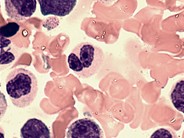

Dysgranulopoiesis - 7.

Hypogranulation: arrow points to a myeloid precursor with relative absence of secondary granules. The cytoplasm takes on a bluish-gray hue.